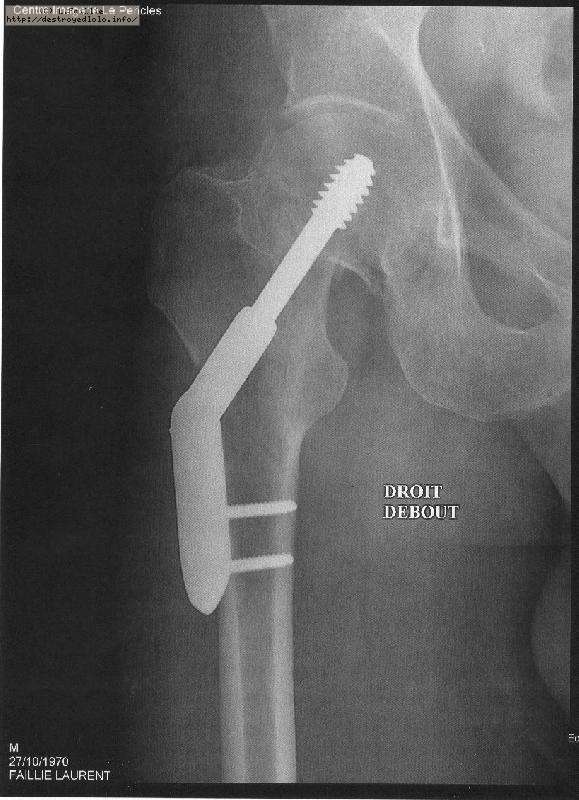

La saison est finie : fracture du col du fémur :(

Pompier, hôpital, 3 mois alités ...